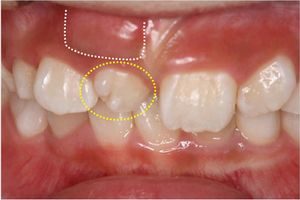

12歳の男の子、前歯がガタガタで出っ歯が気になるので矯正相談に来られました。レントゲン撮影したところ、下顎の第二小臼歯(黄色い丸で囲った部分)が先天的に欠損していて、乳歯がそのまま残っていることが判明しました。両隣りの ...